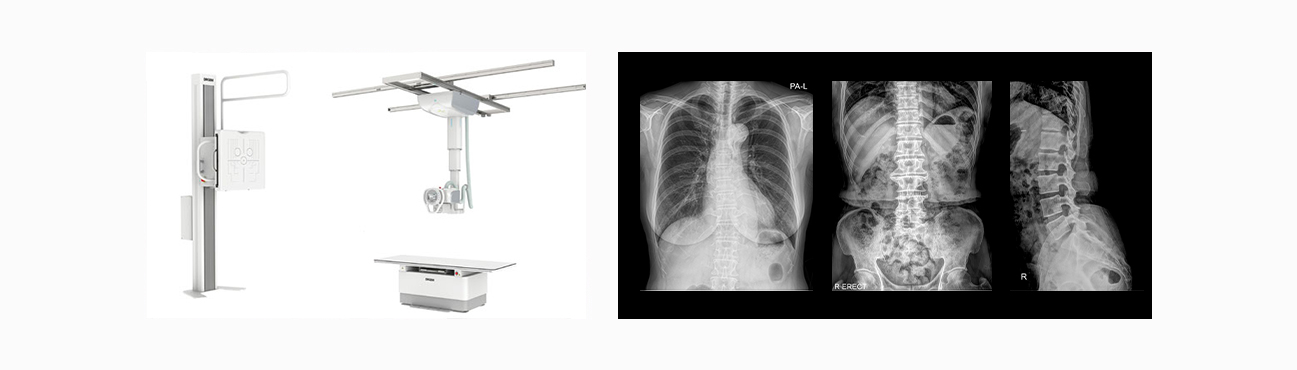

X-ray검사

빠른 시간 내에 세밀한 X선 검사를 통해 간단하고 정확한 진단을 내립니다.

X선을 인체에 투과시켜 촬영하는 검사로 결핵, 폐렴, 신장 결석, 장폐색증, 팔다리 또는 척추 등의 골절진단이 가능합니다.

• 흉부 X-ray촬영 : 결핵, 폐렴 등의 감염성 폐질환, 폐암 또는 폐전이 등의 종양성 폐질환을 진단

• 복부 X-ray 촬영 : 신장 결석, 장폐색증 등의 진단

• 골격 X-ray 촬영 : 팔다리 또는 척추 등의 골절 등을 진단